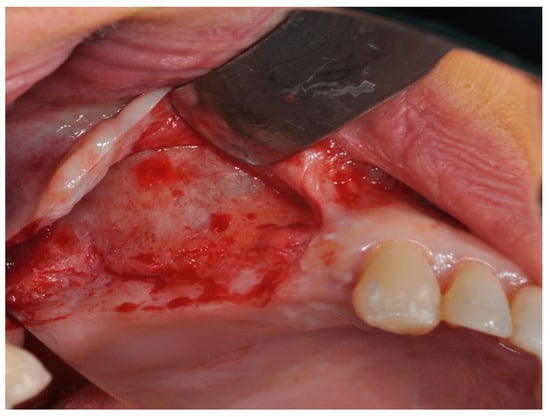

4. Materials and Methods